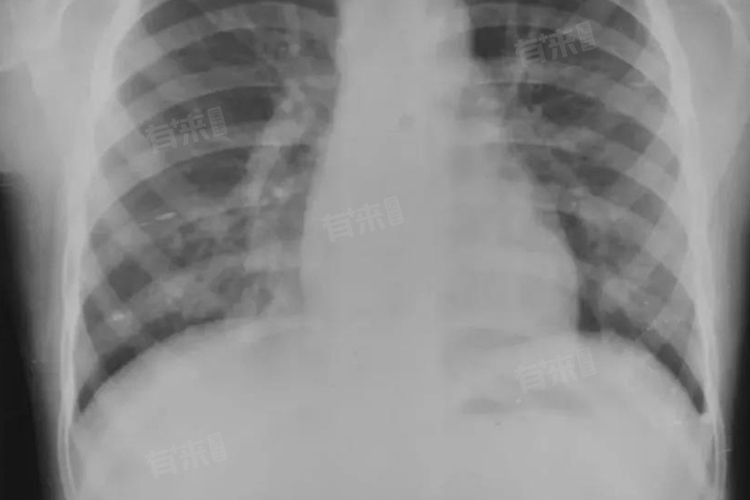

小叶性肺炎是细支气管及其所属肺泡的急性化脓性炎症,症状涵盖发热、咳嗽咳痰等方面,从轻微不适逐渐发展为较为严重的肺部感染表现。

- 医生在听诊时,可在肺部闻及散在的湿啰音,是由于炎症使肺泡和支气管内有渗出物,气体进出时产生水泡破裂音。病情严重时还可能出现叩诊浊音,提示肺部存在实变区域。